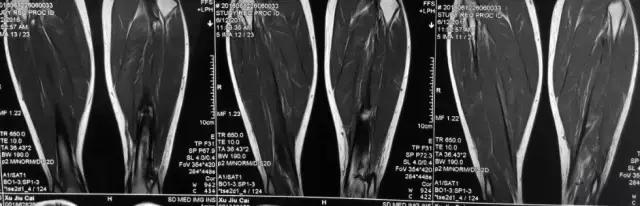

影像检查

诊断:感染。 检查:膝关节MRI,确认伤口窦道是否与髓腔相通。 治疗:1、血沉和C反应蛋白正常,目前无需特殊处理。 2、如果窦道反复出现或血沉和C反应蛋白升高可考虑手术。如证明窦道与髓腔相通,需行扩髓。

核磁示中下段骨髓炎,上面切口处流脓,请问张主任你的意见要上手术吗?

1、是具备手术指征了!也就是说可以手术。 2、并不是必须马上手术。不发热,不红肿、化验都正常也可以换药口服抗生素。